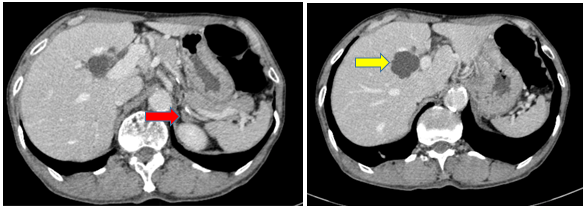

- Chụp CT bụng tháng 10/2024 (trước điều trị)

Hình 3:

Hình ảnh dày cành trong tuyến thượng thận trái 11mm (mũi tên đỏ), gan có vài nang, lớn nhất đường kính 30mm (mũi tên vàng)

- Chụp CT bụng sau điều trị:

Hình 9: So sánh phim chụp CT bụng trước điều trị nốt tuyến thượng thận ~11mm (mũi tên đỏ) đã giảm nhẹ kích thước sau điều trị còn ~9mm (mũi tên vàng)